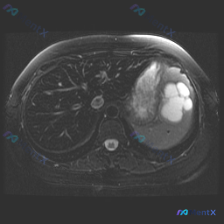

这是一张轴位T2WI,最突出的异常在脾脏:

- 信号:脾实质内有数个类圆形极高信号影,信号强度接近脑脊液,提示是液体(浆液性为主)。

- 形态:边界清晰,但边缘呈分叶状,囊腔之间相互融合或紧邻,不是那种圆钝、孤立的单纯囊肿感。

- 占位效应:病灶体积不小,局部脾实质有受压/被替代的表现。

- 其他背景:肝脏、胰腺(可见部分)信号形态还好,腹膜后没看到明确肿大淋巴结,肠壁也没明显增厚。